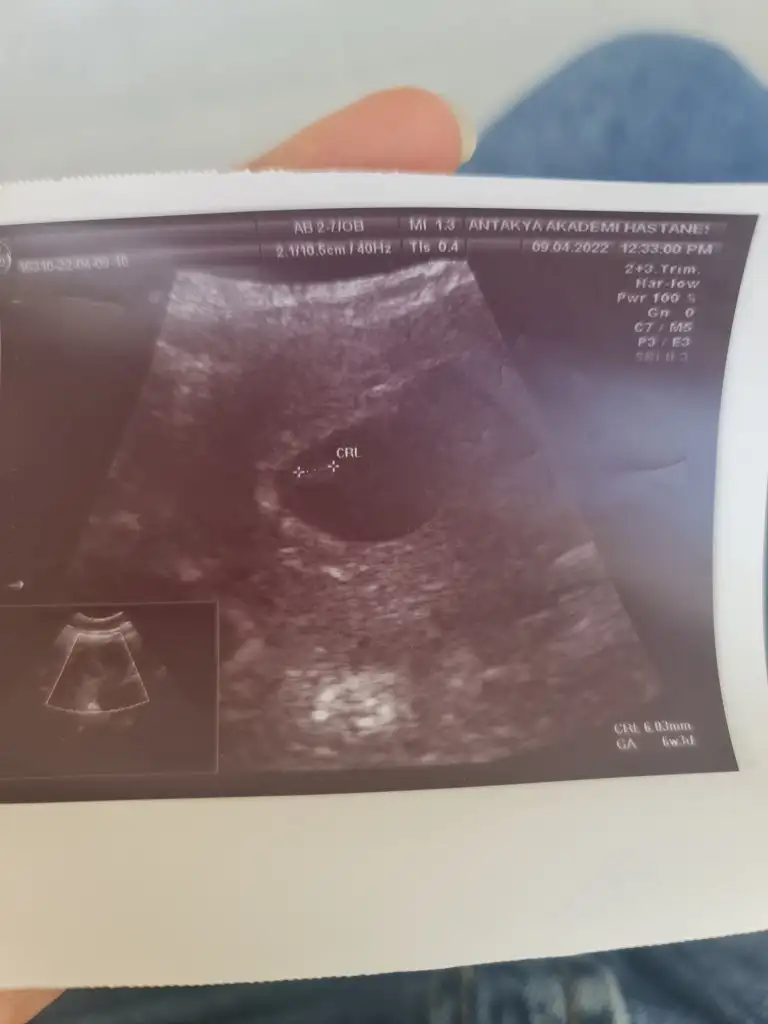

5 ve 14. haftaya kadar olan ultrason fotolarınızı paylaşın. Vajinadan mı yoksa karından mı çekildiğini ve kaç haftalık olduğunu da mutlaka belirtin.